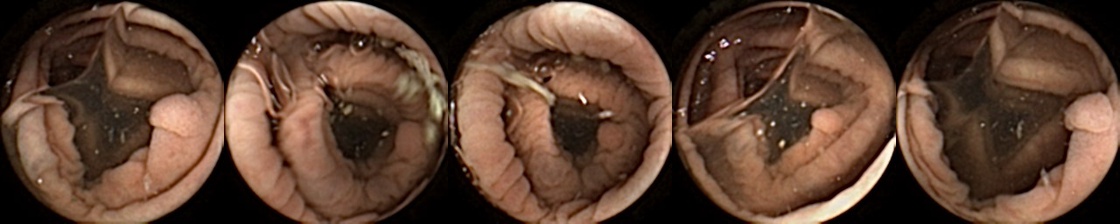

We can additionally consider the confusion matrices from the best MIV model associated with (a) the pretrained ConvNext and (b) SimCLR pretraining using the ConvNext backbone in Figure 5. We note that using SimCLR achieves a better ratio of False Negatives (70) to False Positives (38) as compared to pretrained ConvNext, which has 109 False Negatives and 23 False Positives.

Figure 5: Confusion matrices from the best MIV model associated with (left) the pretrained ConvNext, and (right) SimCLR pretraining using the ConvNext backbone